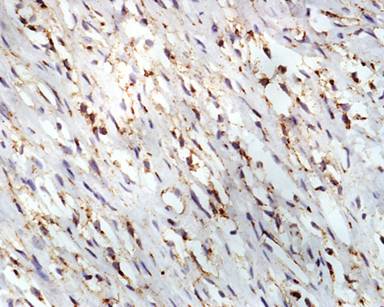

A 11-year-old male presented with complaints of painless hard swelling involving left lumber, umbilical and left hypochondrium of abdomen. According to his mother he was apparently asymptomatic 20 days back when he incidentally noticed firm to hard swelling in left upper abdomen. No history of fever, vomiting, jaundice, weight loss and hematemesis and bleeding per rectum was seen. No family history of a genetic disease was seen. Clinical examination was normal. Body fluid amylase was 4,800 U/L (reference range: 4-234 U/L) and liver function tests were normal. Computed tomography (CT) revealed a large mass measuring 10.0x8.8x7.5 cm in the pancreatic tail, mainly solid but small cystic component (Figure 1). The pancreatic tail mass was well-delimited but not encapsulated. There was no evidence of local invasion or metastasis. The surrounding vessels (celiac trunk, superior mesenteric artery, and splenic and portal veins) were not invaded. The surrounding pancreas was normal. The clinical diagnosis of adenocarcinoma of the pancreas was suspected. Resection of pancreatic tail mass and distal pancreatectomy with splenectomy was performed. Operative findings showed a mass with cyst involving pancreatic tail, adherent to splenic vein and artery, free from stomach and left kidney. The macroscopic examination revealed compressed pancreas measuring 4.0x1.0x0.5 cm, spleen measuring 8.5x6.0x3.5 cm with mesentery measuring 3.0x3.0x0.5 cm. and a well circumscribed, non-encapsulated, dense, mesenchymal tumor measuring 10.0x8.8x7.5 cm with a cystic area measuring 1.5 cm in diameter (Figure 2). Outer surface of the tumor was grey white and lobulated. No lymph node was seen. Histological examination showed a circumscribed tumor arranged in intersecting fascicles infiltrated the surrounding pancreatic parenchyma (Figure 3).Tumor cells are mildly anisomorphal with spindle shaped cells having elongated nuclei with blunt ends and bipolar cytoplasm. Mitosis is infrequent (less than 1-2 per 10 high power fields). Necrosis was not seen. Spindle shaped cells have a regular nucleus and were separated by large amounts of collagen fibers in edematous tissue with some inflammatory cells (Figure 4). The cystic component was seen within the tumor. Spleen showed congestion and focal fibrosis. Immunohistochemical analysis revealed that the tumor cells were strongly positive for beta-catenin (Figure 5), vimentin (Figure 6) and negative for cytokeratin (CK), CD34 (Figure 7), S100, CD68, CD117, smooth muscle actin (SMA) (Figure 8), muscle specific actin, desmin, CD99, Bcl2, anaplastic lymphoma kinase 1 (ALK-1) and human melanoma vlack 45. Proliferation marker Ki67 stained about 2% of the tumor cells. The immunohistochemistry and histopathological features were consistent with a confirmed diagnosis of desmoid tumor. A short term follow-up showed rapid disappearance of the symptoms which had revealed the desmoid tumor. Because of complete resection and the sporadic origin of the desmoid tumors, no corresponding treatment was given. After 10 months of follow-up, the patient is well and normal on clinical examination.

Figure 5. Tumor cells are strongly positive for beta-catenin immunostaining (x40 magnification). |

The negativity of Bcl2, CD34, CD117, MD-M2 and CDK4 expression excluded a solitary fibrous tumor, a gastrointestinal stromal tumor (GIST) or a dedifferentiated liposarcoma [24, 25]. The absence of the mutation of PDGFRA and c-KIT genes exclude the diagnosis of a GIST [26, 27]. In c-KIT negative tumors, mutation in c-KIT or PDGFRA genes can be assessed by molecular pathology which distinguish GISTs from other soft tissue tumors. Solitary fibrous tumors can show striking hyalinization and may be difficult to differentiate from desmoid tumors, especially in those cases composed of only a few vessels with a classical “staghorn pattern.” However, soft tissue tumors typically express CD34, CD99, and Bcl2. Desmoid tumors are believed to be related to clonal myofibroblastic proliferation and to the somatic mutation of the Wnt/beta-catenin gene, leading to the nuclear accumulation of beta-catenin. In our case, positive nuclear immunostaining of beta-catenin was in accordance with these findings and confirmed the diagnosis of a desmoid tumor while the initial diagnosis was adenocarcinoma. This was suggested because of the tumor with cystic component, the tail location and the male gender. A recent study confirmed that nuclear beta-catenin immunostaining is competent in distinguishing desmoid tumors from other benign and malignant fibroblastic and myofibroblastic lesions [28]. Inflammatory myofibroblastic tumors have more cellular with moderate to marked nuclear atypia and inflammatory cells in the background. Anaplastic lymphoma kinase-1 positive and negative beta-catenin [29] immunohistochemistry helps in the diagnosis of inflammatory myofibroblastic tumors [30]. Hyalinization in retroperitoneal fibrosis is more prominent and often associated with marked lymphoplasmacytic infiltrate [31].